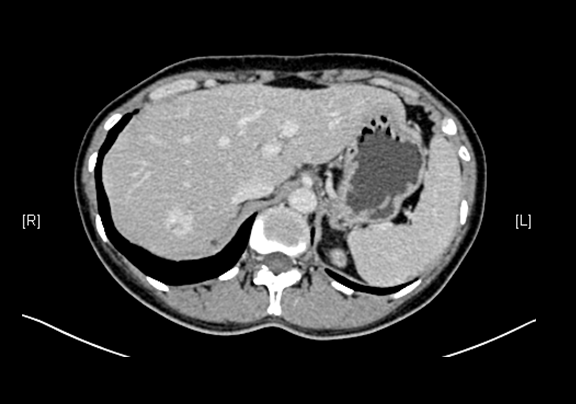

辅助检查:2015-12-07

上腹部增强CT示:肝右叶海绵状血管瘤可能性大;肝囊肿;左肾上极肿瘤可能性大;双肾多发囊肿。

术前CT检查:

静脉期